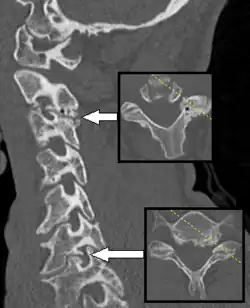

Axial skeleton and extremities

For the axial skeleton and extremities, CT is often used to image complex fractures, especially ones around joints, because of its ability to reconstruct the area of interest in multiple planes. Fractures, ligamentous injuries, and dislocations can easily be recognized with a 0.2 mm resolution.[71][72] With modern dual-energy CT scanners, new areas of use have been established, such as aiding in the diagnosis of gout.[73]

Multiplanar reconstruction (MPR) is the process of converting data from one anatomical plane (usually transverse) to other planes. It can be used for thin slices as well as projections. Multiplanar reconstruction is possible as present CT scanners provide almost isotropic resolution.[109]

MPR is used almost in every scan. The spine is frequently examined with it.[110] An image of the spine in axial plane can only show one vertebral bone at a time and cannot show its relation with other vertebral bones. By reformatting the data in other planes, visualization of the relative position can be achieved in sagittal and coronal plane.[111]